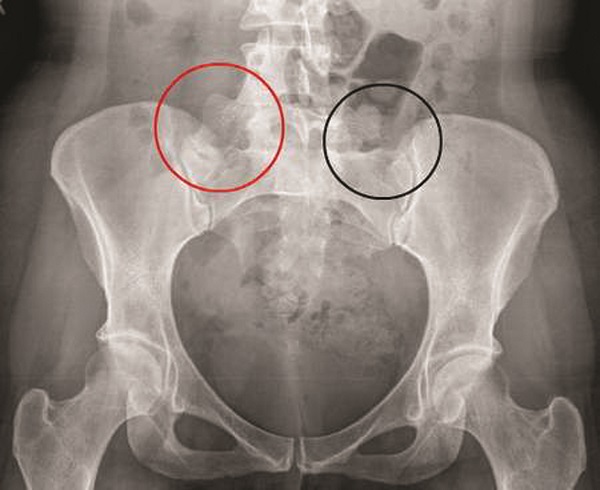

Viêm khớp cùng chậu là tình trạng vùng khớp nối giữa xương sống và xương chậu nằm ở gần hông gặp phải tổn thương khiến vùng khớp này trở nên tê cứng, đau nhói và đau âm ỉ khi lâu ngày không được chữa trị. Đây cũng là một trong những biểu hiện và nguyên nhân gây nên bệnh viêm cột dính khớp.